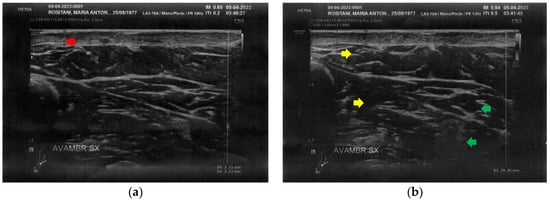

3.1. Basal Imaging Evaluations

3.2. Imaging Evaluations After the Treatment